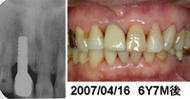

![]() 写真6■同患者の6年7ヵ月後 冠装着時とほとんど変わらぬ審美性を維持している。 |

私は歯肉縁下の形成の深さを、近遠心で0.8~1.0mm、唇側で0.6~0.8mm、口蓋側で0.3~0.4mmを標準としている。もともと支台は細いので、さらに削って細くするのではなく、必要なら少し浸麻をしてライトシャンファーまたは槍状のダイヤモンドバーを使用してインプラント周囲粘膜を形成するつもりで支台歯形成をしている。ジンパックで止血し、そこまでシリコン印象剤で印象し、Finishing Line から近遠心側と唇側でただちに歯冠部を豊隆させ、できるだけ自然に近いEemergence Profile を作ることに尽きるように思われる。また、歯肉縁下までの形成だけでは歯肉縁の Scallop形態の連続性の再現が困難なものは,歯肉切除術のようなSoft Tissue Management が必要となるが、それらにより2ピースに負けない審美性が得られる。そのような審美性の工夫を心がけて治療し経過観察をおこなっているが、大部分の症例で装着時のみならず、経年的にも審美性をほとんど損なうことなく経過している。審美性の問題はインプラントにおいてますます重要な要素になって行くのは間違いない。